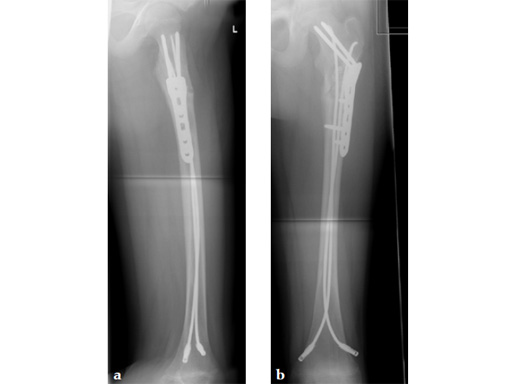

Case 1: LCP PHP 130. A 15-year-old boy sustained a refracture of a pathological fracture of the subtrochanteric region following a severe trauma, previously fixed with ESIN , diagnosis: juvenile bone cyst.

Case provided by Theddy Slongo, Bern, Switzerland